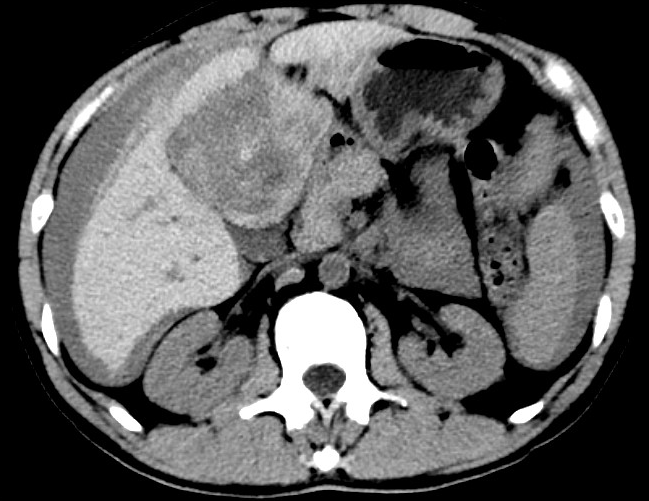

放下電話的白葦急赴消內(nèi)三搶救室會(huì)診,經(jīng)仔細(xì)查體、對患者腹部CT進(jìn)行詳細(xì)閱片、綜合評估患者后,考慮患者是肝占位破裂出血?;颊卟∏槭志o急、一刻也不容耽誤,需立刻急診行肝動(dòng)脈造影 栓塞術(shù)進(jìn)行止血治療,在與患者家屬溝通后,立即通知消化介入室準(zhǔn)備急診手術(shù)。

入手術(shù)室時(shí),患者神志迷糊,口唇干燥、重度貧血貌,心電監(jiān)護(hù)提示:心率140-160次/分,血壓70/43mmHg,這是失血性休克的表現(xiàn)!白葦快速建立靜脈通道緊急給予輸血,升壓,止血等液,立即給予肝動(dòng)脈造影,術(shù)中發(fā)現(xiàn)肝左葉疑似腫瘤病灶、病灶周圍血管分支有造影劑外溢,考慮血管破裂出血,迅速給予栓塞微球進(jìn)行肝動(dòng)脈栓塞。整個(gè)手術(shù)過程不足20分鐘,術(shù)后即刻患者心率降至100-110次/分、血壓升至90/60mmHg。

術(shù)后給予積極抗炎,止血,保肝、利尿等對癥治療,復(fù)查血常規(guī)提示活動(dòng)性出血停止后,在超聲引導(dǎo)下行腹腔穿刺引流術(shù),術(shù)后3天共引流出血性腹水約4000ml?;颊呓?jīng)復(fù)查各項(xiàng)指標(biāo)均趨于正常,復(fù)查CT提示腹腔積血已基本吸收,患者康復(fù)出院。